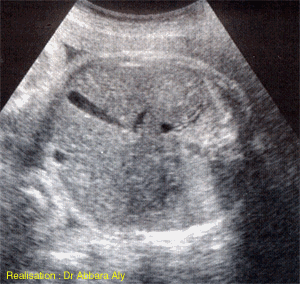

Coupe échographie fœtale abdominale transverse dirigée vers

le foie et la vésicule biliaire